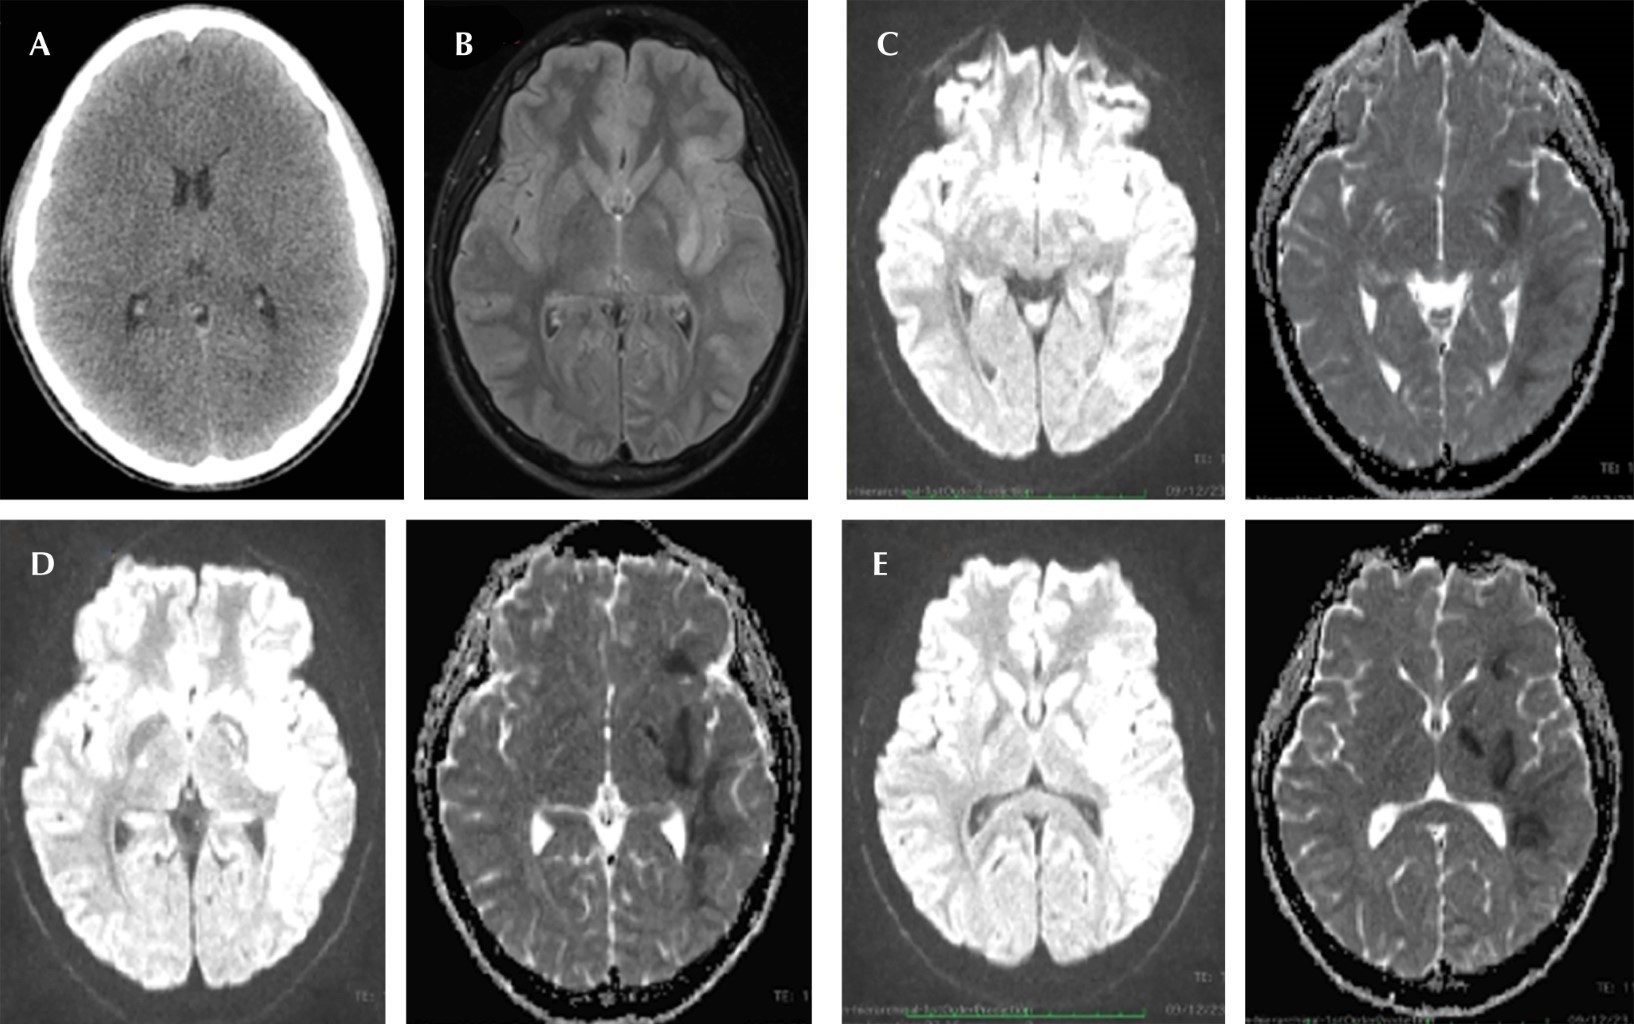

A valoración en el servicio de urgencias se realiza TAC simple de cráneo, la cual se encuentra sin alteraciones, sin áreas de sangrado con adecuada diferenciación de sustancia gris y sustancia blanca, por lo anterior se le solicitó resonancia magnética (RM), secuencias de difusión y coeficiente de difusión aparente (ADC) muestran sitios de restricción en núcleos de la base involucrados: globo pálido y lenticular izquierdo, cambios yuxtacorticales (Figura 3).

Figura 3